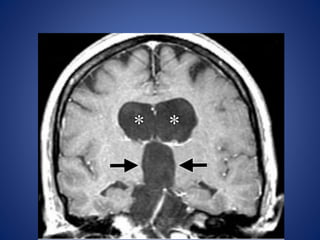

Arachnoid Cyst

Arachnoid cysts account for roughly 1% of intracranial masses, with

nearly 10% occurring in the sellar-suprasellar region.

Imaging Features.—

• Arachnoid cysts are smooth, well-circumscribed lesions that

classically follow the attenuation and signal characteristics of

cerebrospinal fluid unless complicated by hemorrhage.

• There is no associated enhancement, although there may be

associated mass effect or remodeling of the adjacent calvaria.